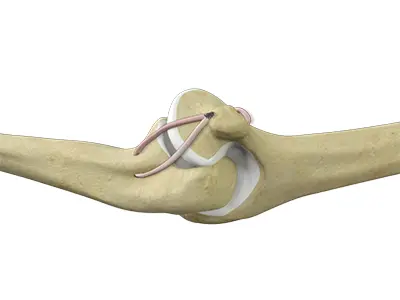

UCL Reconstruction (Tommy John Surgery)

Commonly called Tommy John surgery, this procedure involves reconstructing a damaged ligament on the inside of the elbow called the ulnar

Elbow Ligament Reconstruction

The elbow joint is supported by the ulnar collateral ligament, radial collateral ligament, and the annular ligament.